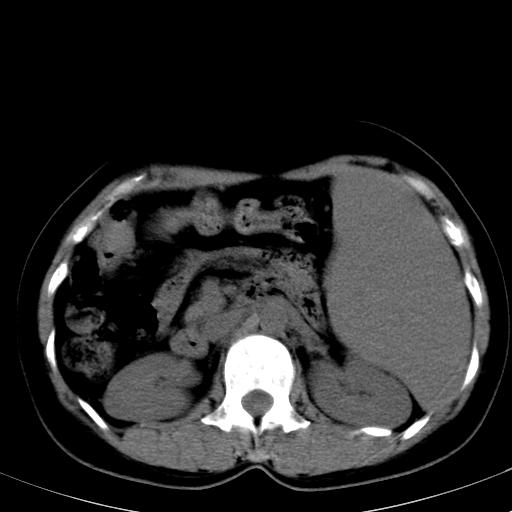

标题: CT19818:女40,脾大伴贫血,无肝炎病史 [打印本页]

标题: CT19818:女40,脾大伴贫血,无肝炎病史

血常规血红蛋白102,

骨穿,诊断再障,无其他病史

脾大符合临床诊断(再障)。

巨脾。

肝硬化、门脉高压、脾大。再障+肝硬化促成巨脾。

肝叶比例失调,肝左叶明显增大,包膜欠规整,脾大,支持考虑肝硬化、门脉高压、脾大。